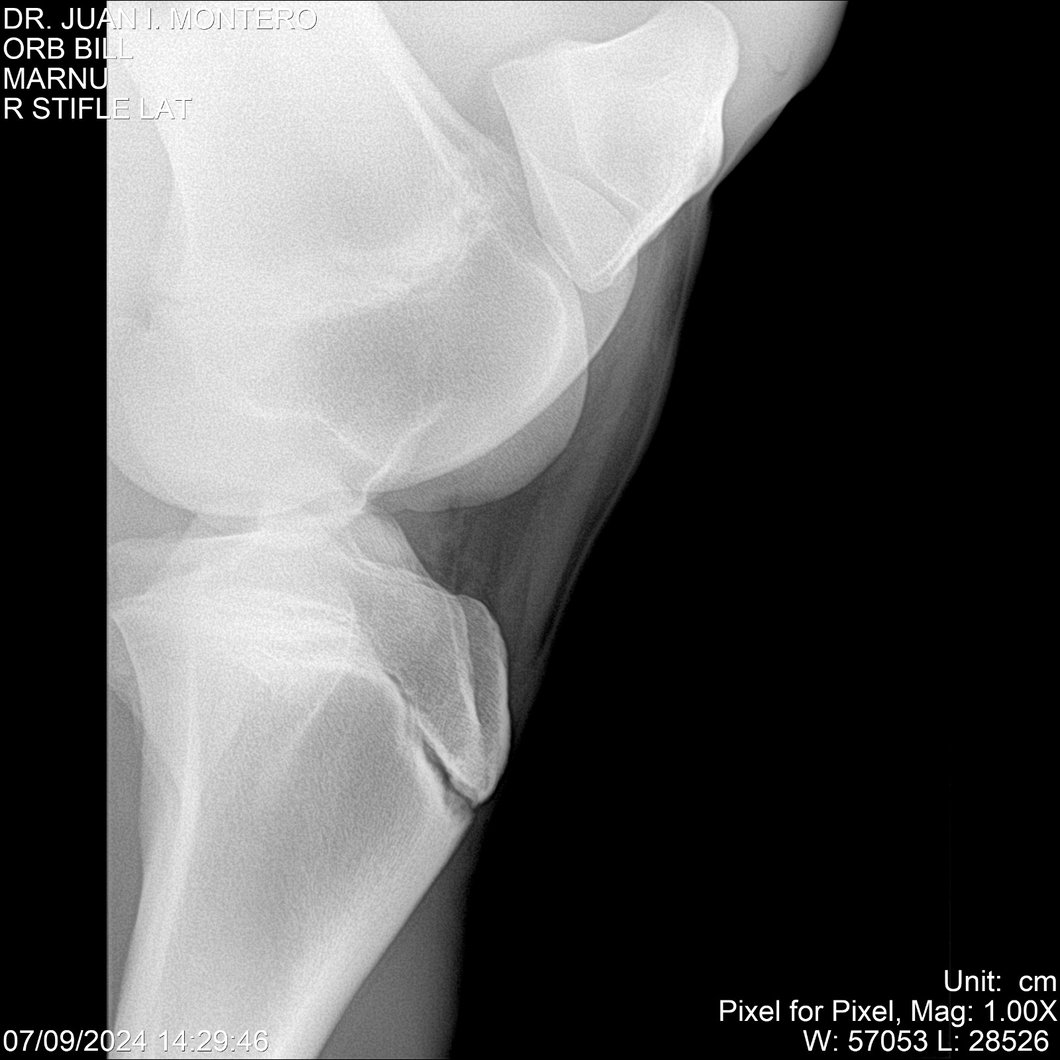

LOTE 7, ORB BILL 🔥 🔥 🔥 Lote Anterior Volver al remate Lote Siguiente Ficha Contacto Montevideo - Ficha del Lote Identificador: #282523 Categoría: Yeguarizos Montevideo - 83 Visualizaciones ClicData Contacto Empresa: Abelenda N. R., Walter Hugo Nombre*: Teléfono* : E-mail* : Mensaje Enviar Registrese gratis Este contenido Exclusivo está disponible sólo para usuarios registrados Ingresar